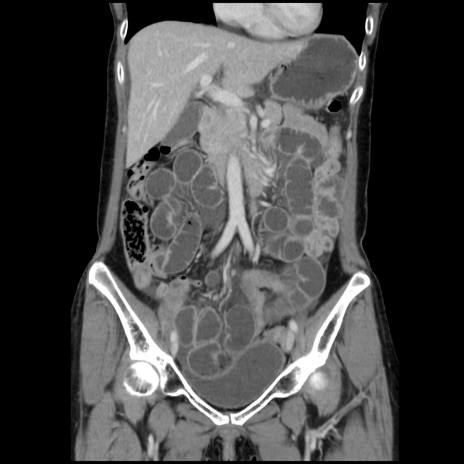

症例32(冠状断像)

【症例】40歳代 女性

【主訴】上腹部痛、嘔気・嘔吐

【現病歴】約9時間前頃から急に上腹部痛、嘔気、嘔吐が出現。改善しないため救急要請。

【既往歴】子宮頚癌(広汎子宮全摘術、放射線療法)、腸閉塞

【身体所見】腹部:平坦、軟、腸雑音亢進、上腹部を中心に腹部全体に圧痛あり。

【データ】WBC 8400、CRP 0.03